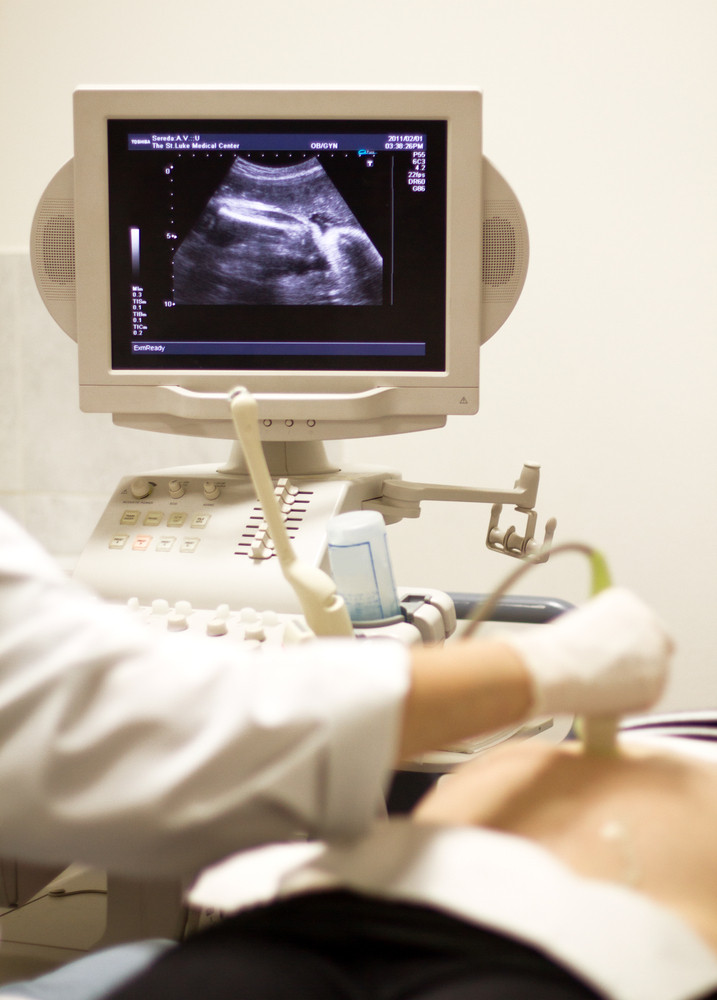

Cần thiết của chụp hình ảnh

Các bệnh nhân dùng chụp tia X, quét CT và chụp hình ảnh y học hạt nhân bao gồm PET/CT và PET/MRI đều có khả năng phơi nhiễm các bức độ bức xạ. May sao tiến bộ công nghệ đã làm giảm đáng kể mức độ phơi nhiễm bức xạ xuống mức thấp nhất có thể so với cách đây nhiều năm. Ngay cả khi phơi nhiễm bức xạ là rất nhỏ, nhưng nhiều người vẫn mơ hồ sợ hãi và vô hình làm trầm trọng căn bệnh ung thư mà họ đang sống chung.

Trên thực tế, phơi nhiễm bức xạ từ hình ảnh y học là không đáng kể trong quá trình điều trị y tế. Viện phí cũng là một gánh nặng. Chụp hình ảnh càng đắt tiền, bệnh nhân càng tìm cách tránh nó. Nhưng chụp hình ảnh đắt tiền cũng giống như người ta xài điện thoại thông minh, thông số kỹ thuật của điện thoại càng tốt thì nó càng đắt.

Chụp hình ảnh y học hạt nhân tương đối tốn kém do máy quét cũng như chất bức xạ cần để chụp, mà những chất bức xạ này lại phải được đặt hàng đặc biệt và không có sẵn.

Sau rốt, bệnh nhân cần phải hiểu rằng các bác sĩ sẽ chọn những phương pháp hình ảnh để giúp chẩn đoán, lập kế hoạch, đánh giá và theo dõi các điều kiện của bệnh nhân. Rủi ro và lợi ích của mỗi hình ảnh luôn được đánh giá cẩn thận trước khi bệnh nhân tiếp cận với chúng.